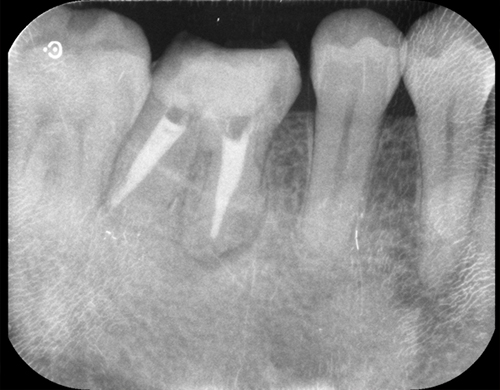

根管治療(外科的歯内療法)の症例

| 年齢・性別 | 50歳・男性 |

|---|---|

| 主訴 | 歯ぐきにできものができた |

| 治療期間 | 2ヶ月 |

| 治療内容 | 歯根端切除術 奥歯に根尖病変を認め、サイナストラクトと呼ばれる膿の通路ができていた。まずは根管治療を行い歯の内部の感染源を可及的に除去したが、サイナストラクトが消失しなかったため、根尖孔外に感染源があると考え歯根端切除術を行った。 結果、サイナストラクトは消失し、一年後の経過も良好である。 |

| 治療費用(総額) | 保険適応 |

| 治療のメリット | 歯を保存できる |

| 治療のデメリット・リスク | 外科処置が必要 |